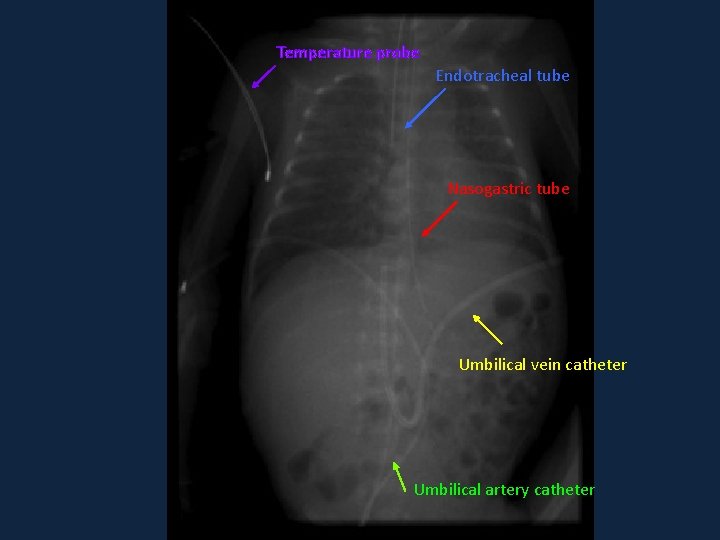

Systematic approach ►A ►B ►C ►D ►Extras: ►Check for lines and tubing

Temperature probe Endotracheal tube Nasogastric tube Umbilical vein catheter Umbilical artery catheter